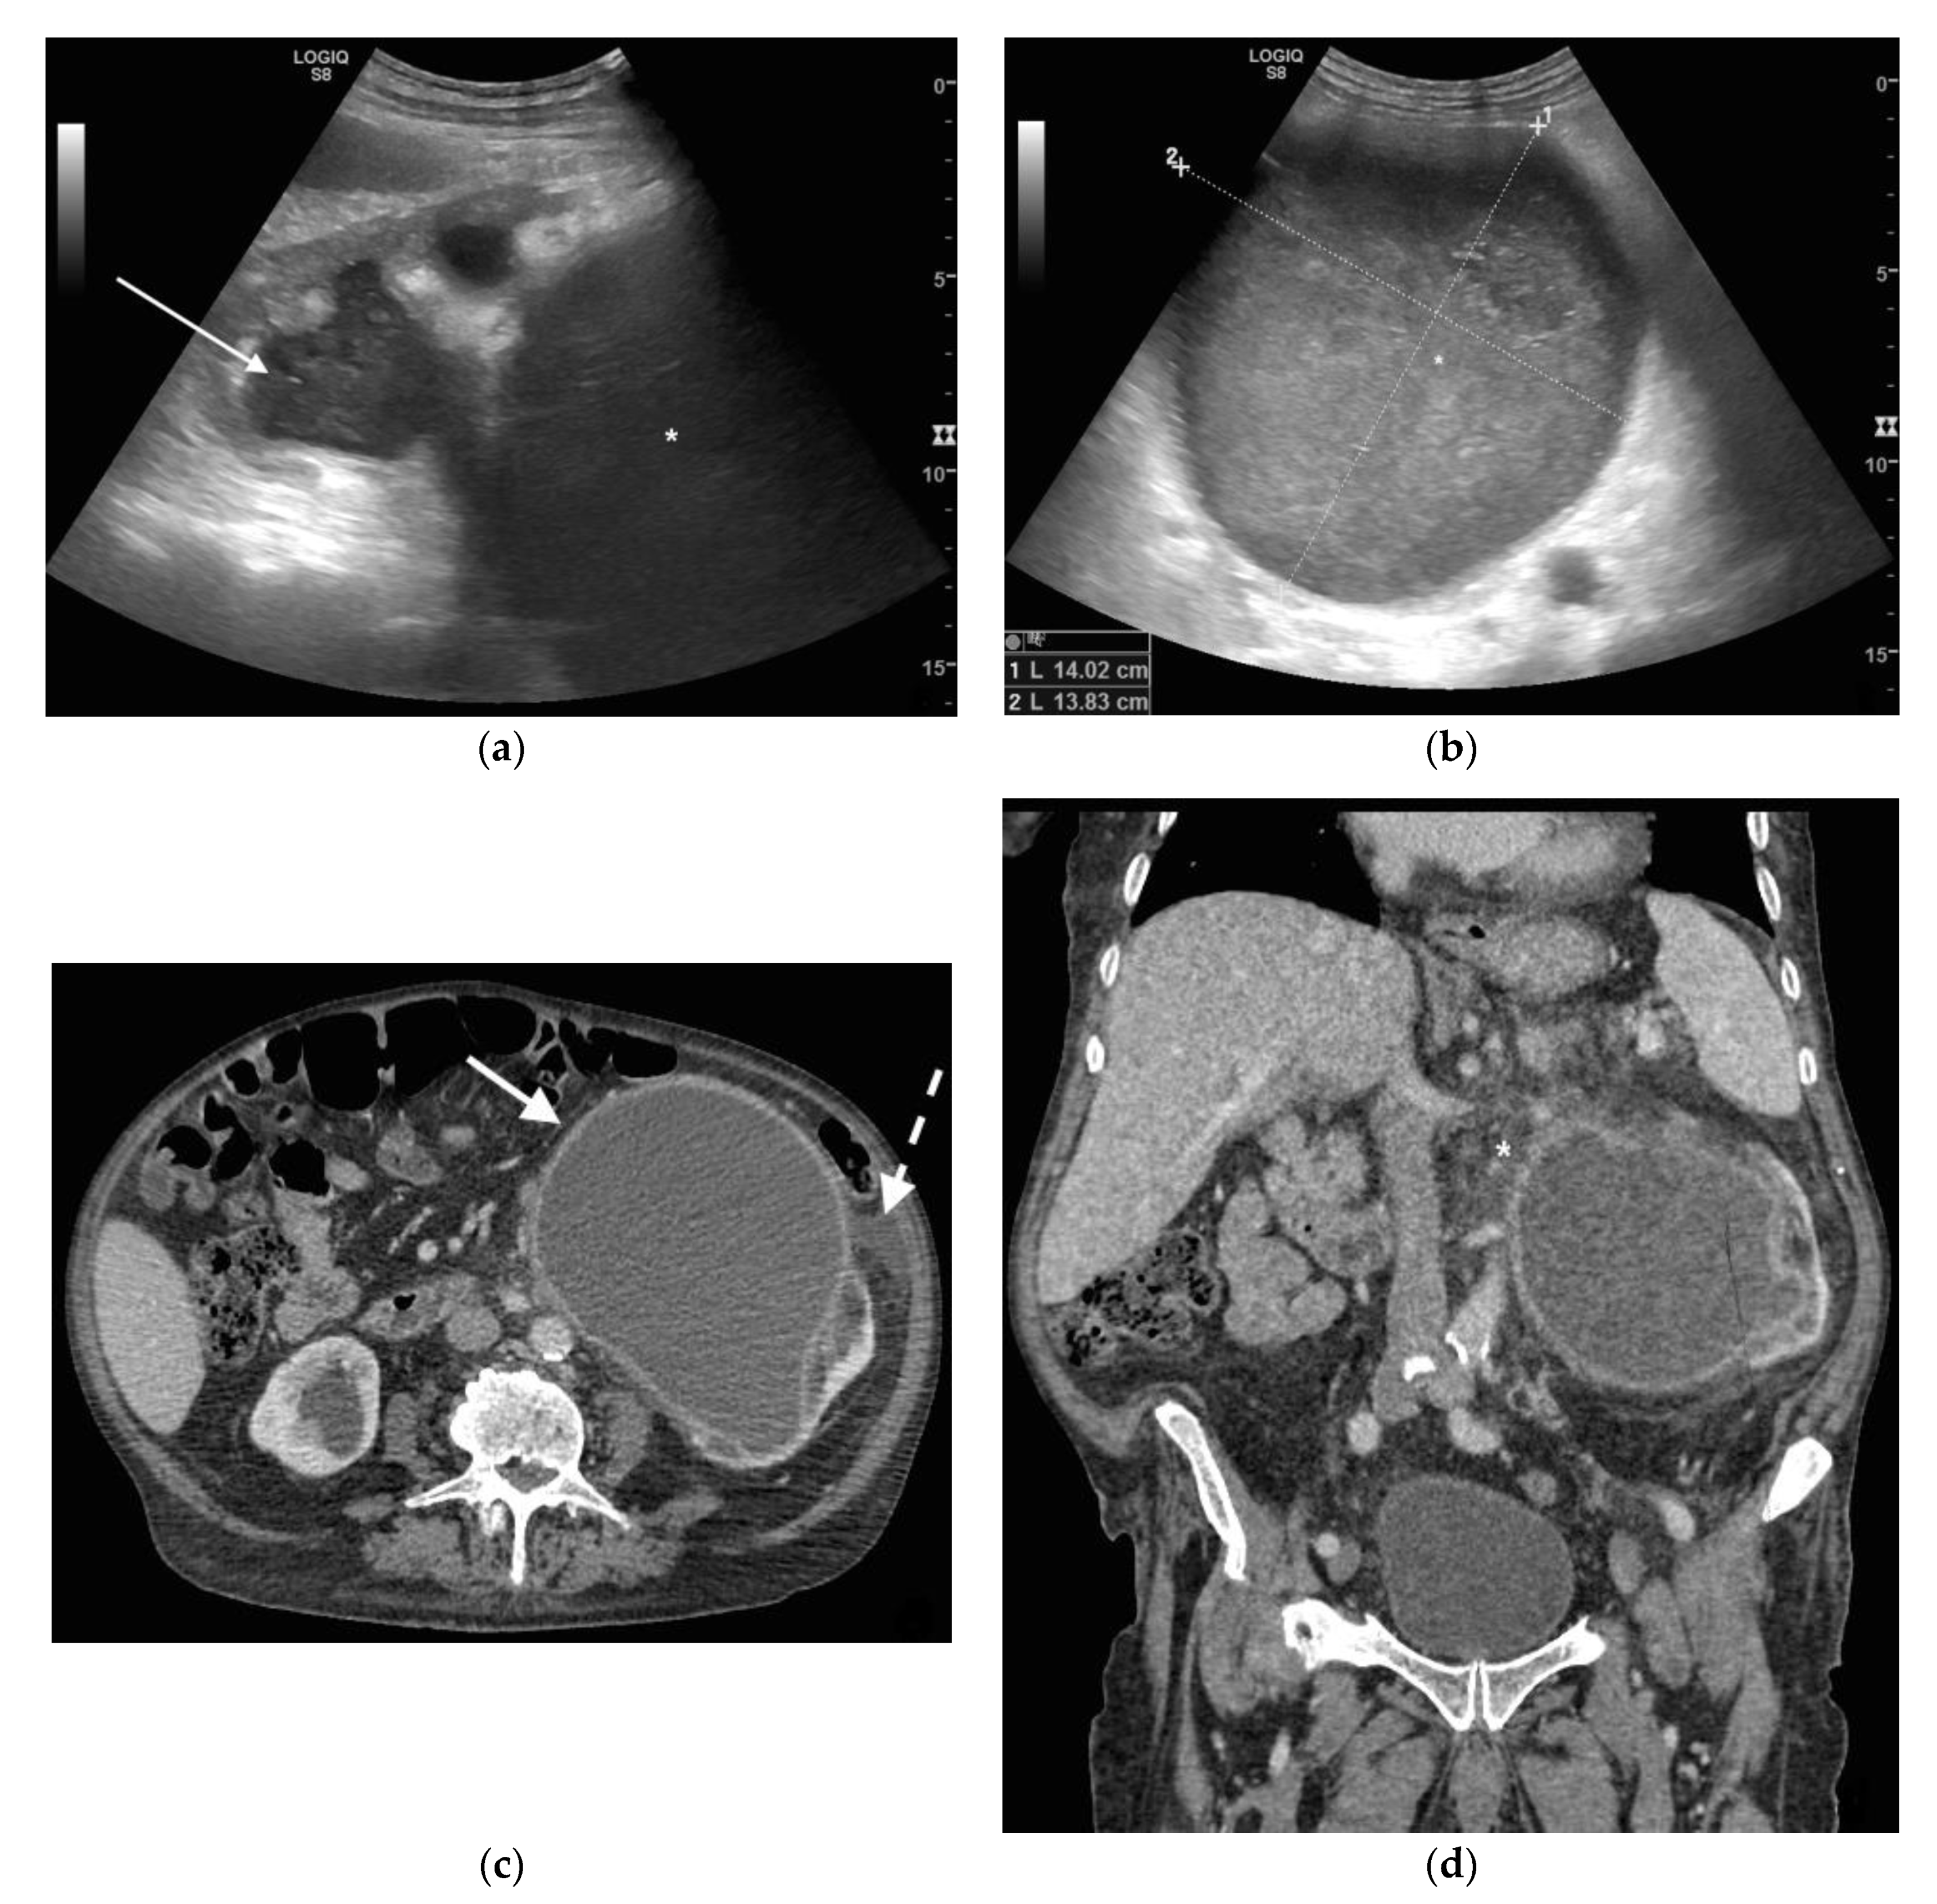

3. Ultrasound

4. CT